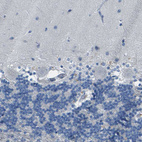

Immunohistochemistry analysis in human liver and skin tissues using HPA013547 antibody. Corresponding CYP2C8 RNA-seq data are presented for the same tissues.